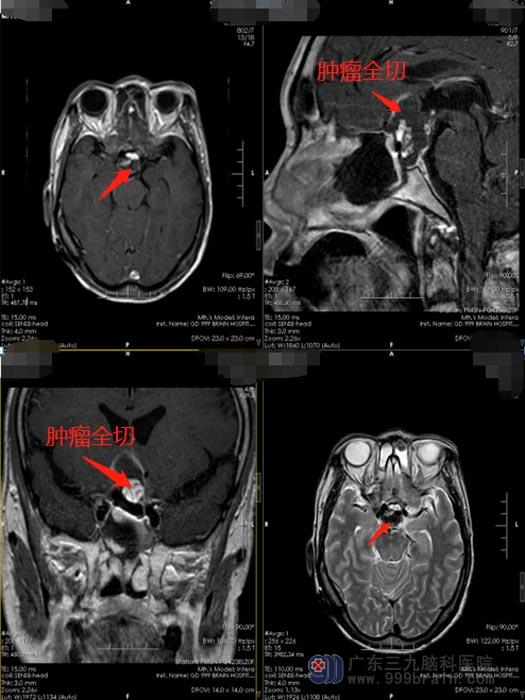

郑大哥有明确的手术指证,应尽早手术,否则病情会向更为严重的方向发展。完善相关的术前准备后,由鲁明主刀为患者行全麻下“经鼻蝶鞍区占位切除术,”手术非常成功,术中出血少。术后郑大哥恢复很快,也没有出现手术并发症。